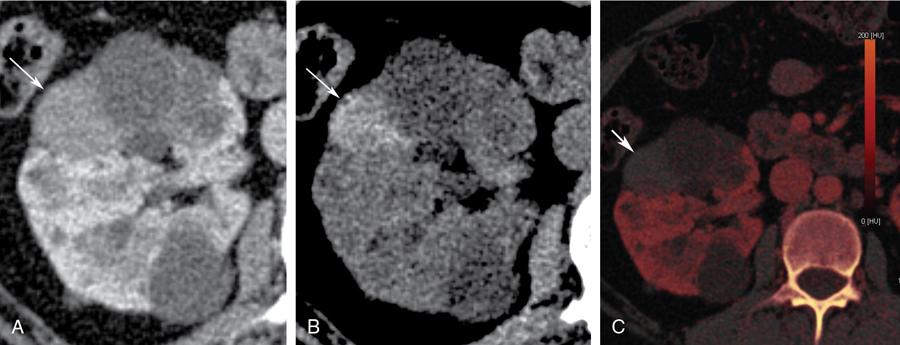

Bosniak category III

- Imaging: Bosniak type III cysts are indeterminate cystic masses with thick irregular wall or septae, showing measurable enhancement (Fig. 10.12.1.5). Apart from RCC, differential for Bosniak type III cysts are cystic nephroma (Fig. 10.12.1.6), benign multiloculated cyst, mixed epithelial and stromal tumour (MEST), renal abscess and haemorrhagic cyst.

- Risk of malignancy: 30%–100%.

- Recommendations: Biopsy carries increased risk of false-negative results due to small volume of tumour cells within the cyst. Thus, usual recommendation for type III cysts is surgical resection.